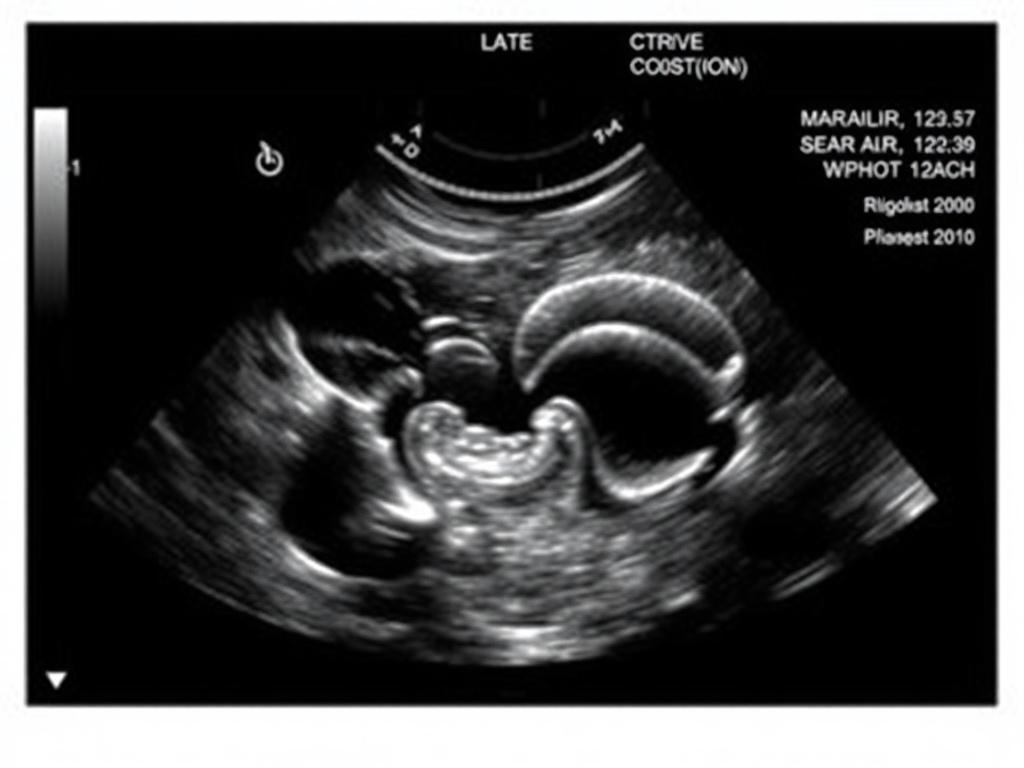

Трансвагинальное УЗИ органов малого таза – это ультразвуковое исследование, при котором датчик вводится во влагалище для детального осмотра матки, яичников, шейки матки, маточных труб и окружающих структур.

- Позволяет оценить структуру эндометрия, фолликулы, ранние сроки беременности.

- Беременность на ранних сроках